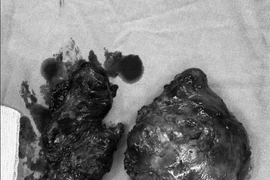

Bướu giáp khổng lồ là bệnh lý hiếm gặp, khối u kích thước lớn ảnh hưởng đến thẩm mỹ và chất lượng cuộc sống như gây khó nuốt, khó thở, run tay, khàn giọng… Phẫu thuật bướu giáp khổng lồ tiềm ẩn nhiều nguy cơ và tai biến.

Bệnh nhân S.B. 20 tuổi (Gia Lai) có khối bướu giáp từ nhỏ, nhưng không điều trị, gần đây bướu to chèn ép khiến anh khó thở, nuốt khó, không thể cúi,...